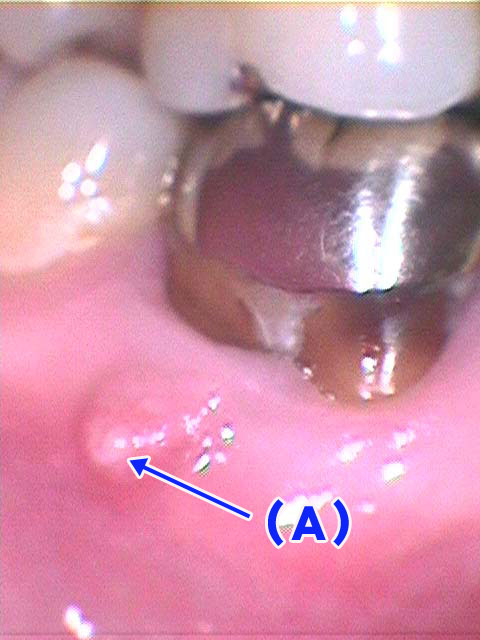

5-1.CCD術野画像拡大システム+画像データベース

根管治療は通常3mm程度の治療をするために肉眼で十分に観察することは困難です。信頼性の高い治療を行うためには治療対象の視野拡大が必要です(Photo-5)。このためには対象領域をCCDカメラと高解像度画像システムによって最大400倍程度まで拡大、治療を行います。

また、これらの画像情報は患者さんの病歴画像としてFDC統合化医療情報システムにデータベース化されています。